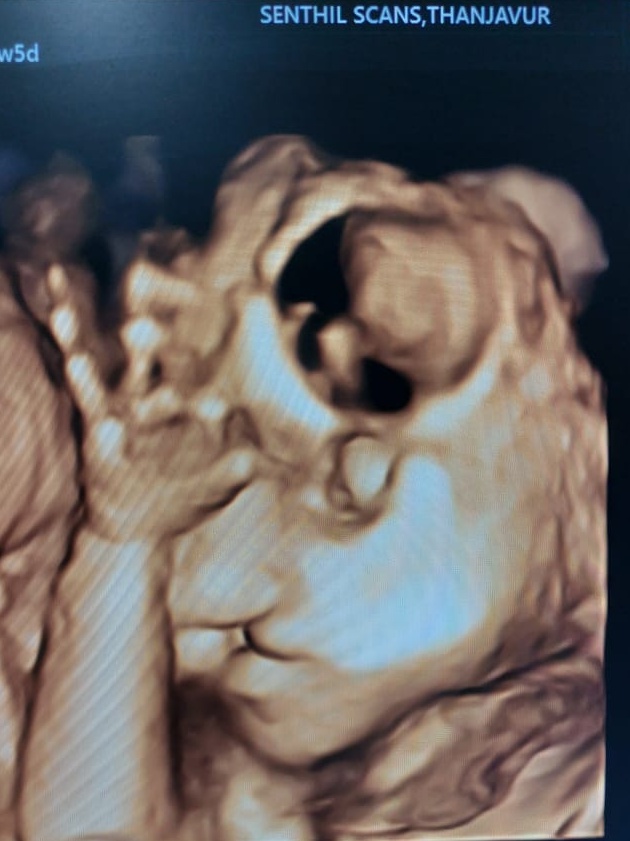

Cleft Lip